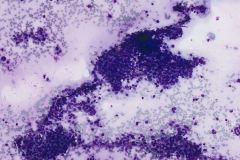

Specimen Type: FNA of Station 7 Lymph node, Diff-Quik and Papanicolaou Stained smears, ThinPrep® Non-Gyn cytology, Formalin-Fixed Cell Block

Cytologic Diagnosis: Positive for Malignant Cells, Metastatic Carcinoma of Breast Origin. The malignant cells are positive for GATA3, AE1/AE3 and estrogen receptor. P40, TTF-1 and Napsin A are negative.

Ductal breast carcinoma specimens are highly cellular and consist of a variety of cell arrangements. The cells will commonly be seen as poorly cohesive clusters, some isolated single cells, and rare sheets of cells. These specimens will have enlarged and hyperchromatic nuclei that are eccentrically placed and often protruding from the cytoplasm. The chromatin has a bland appearance, ranging from finely to coarsely granular, with prominent, irregularly shaped nucleoli. Myoepithelial cells sitting on top of or lining the ductal breast cells are helpful in determining if the specimen is benign and should not be present in IDC specimens. The background of IDC is usually clean, but inflammation, blood, and granular debris may be observed.1,14 Immunohistochemistry (IHC) markers that can be used to stain for ductal breast carcinoma are Ki-67, p63, CK5/6, ER, Mammaglobin, GCDFP-15, E-Cadherin and GATA3. Double staining for cytokeratin, smooth muscle myosin heavy chain, Calponin, and/or p63 is helpful for determining if myoepithelial cells are present in the specimen.1,15 In the current case study, the patient’s specimen presented with marked cellularity consisting of a population of both 3-dimensional clusters of cells and many dyshesive single cells. In the smaller 3-dimensional clusters, some of the cells can be seen forming glandular structures and some look as if they are molded together. The nuclei are enlarged, eccentrically placed, and have a mix of both smooth and irregular nuclear contours. The cells all have high N/C ratios and there is a moderate amount of anisonucleosis. The chromatin has a predominantly hyperchromatic appearance, is finely granular and large prominent nucleoli can be observed. The cytoplasm is scant, has well-defined cytoplasmic borders, and is finely vacuolated. Mucinous vacuoles in the cytoplasm can be seen in the larger 3-dimensional clusters of cells. Crush artifact and necrosis can be observed in the background.